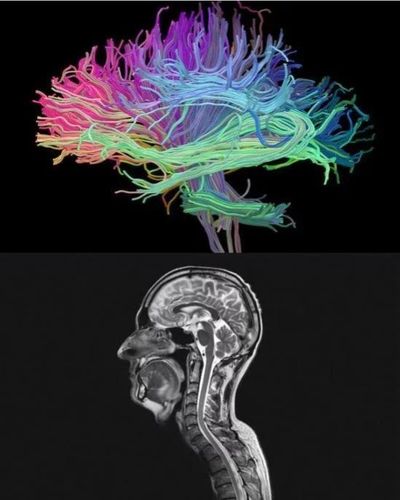

弥散张量成像(dti),主要应用在检测脑白质的发育,成熟及生理性老化

脑白质位置

脑灰质和脑白质

脑白质脑灰质解剖

脑白质和脑灰质图片

脑白质解剖

脑灰质和脑白质解剖图

脑白质解剖图